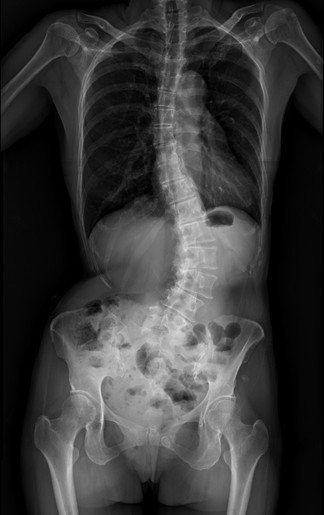

【記者張原銘、張皓傑台中報導】55歲的黃小姐年輕時即被健檢醫師提醒有脊椎側彎,但多年來未加以治療。近兩年症狀明顯惡化,出現劇烈腰背疼痛、下肢麻痺與腫脹,夜間常因疼痛難以入眠,甚至影響行走能力與工作生活品質。經友人推薦,黃小姐前往臺中市立老人復健綜合醫院(簡稱中醫大市醫)骨科就醫,經微創脊椎中心助理副院長張建鈞醫師評估後,決定接受3D導航微創脊椎矯正手術。術後脊椎側彎角度由47度矯正至10度,身高增加約5公分,困擾長達25年的病痛大幅改善,終於能安穩入睡。

張建鈞醫師指出,患者因長期未治療,脊椎側彎角度已達48度,屬於中重度退化性脊椎側彎,且合併二尖瓣膜脫垂的心臟病史,若採傳統開放式手術,手術風險相當高。經完整影像評估與跨科討論後,醫療團隊建議採用「微創前開3D導航矯正手術」,由身體側邊的小切口進行矯正與支撐重建,在不大幅破壞背部肌群的情況下完成手術,有效降低出血量與併發症風險。術後恢復快速,約4至5天即可出院,疼痛亦明顯減輕。黃小姐笑說,術後穿著背架反而帶來前所未有的安全感,甚至捨不得太快卸除。

共同執行手術的骨科部副部長林琮凱醫師表示,脊椎側彎(Scoliosis)並非單純姿勢不良,而是脊椎向側面異常彎曲,並伴隨椎體旋轉變形。臨床上以Cobb角度作為診斷依據,超過10度即可確診。若長期未妥善處理,可能引發慢性疼痛、神經壓迫,甚至影響心肺與內臟功能。常見類型包括幼年型、非特異型、退化性與神經肌肉型,其中退化性脊椎側彎多好發於中老年族群,因進展緩慢而容易被忽略。